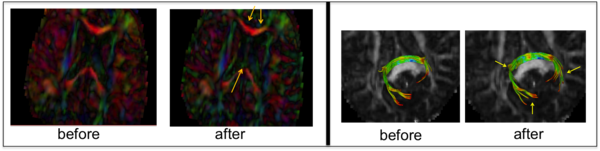

The correction results show visible improvement in contrast within the cingulum and fornix tracts (left) and fiber tractography of splenium (right).

We have proposed new QC step for detecting drop-out signal intensities which can be caused by mechanical vibration artifacts. This step detects and potentially removes these residual artifacts that are not commonly detected in the individual DWIs. The artifacts appear in color-FA images in either widespread or local dominant direction ( see Fig?? ). In order to detect such artifacts, we proposed a new approach via the entropy of the Principal Direction (PD) histogram computed over the major region of the image (e.g. the full brain). Given a prior knowledge of expected entropy values for acceptable scans, the quality of the DTI image is categorized into acceptable, suspicious and highly suspicious/rejection categories using calculated the standard scores.

For our correction step, we employed a simple, iterative leave-one-out-strategy over all individual DWI images by recomputing DTI images and correspond- ing entropies. At each iteration, the DWI with maximal improvement is removed and all leave-one-out entropies are recomputed. This process is continued until either the z-score is in acceptable range or a maximum threshold for exclusion is reached.